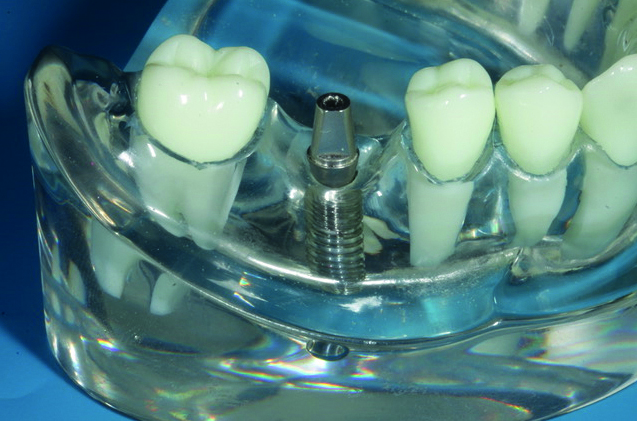

- Ratgeber Zahnarztliche Implantate Fur Patienten Prof Dr Dr P Tetsch Und Dr J Tetsch M Sc M Sc , Herausnehmbarer Zahnersatz Ist Besonders Stark Gefährdet, Dass Dieser Fallengelassen Wird Oder Dass Es Zu Irgendwelchen Fehlbelastungen.

- Bei Zahnprothesen Sieht Man Klammerbruch Ankerzahnverlust Oder Prothesenbruch Dentalnews . Abgestützt Auf Eigene Zähne, Zahnimplantaten Oder Dem Zahnlosen Kieferkamm.

Zum einen sind die metallischen befestigungsklammern im gebiss sichtbar, was von vielen menschen als unschön. Zahnersatz unterscheidet man zwischen herausnehmbarem und festsitzendem. Zahnersatz füllt ihre lücke bei zahnverlust » erfahren sie bei dentolo alles zu: Unter dem begriff zahnprothese wird in der zahnmedizin die herstellung von zahnersatz mit ersatzzähnen für fehlende natürliche zähne zusammengefasst. Tacohan zähne zahnersatz unterkiefer quick zaehne provisorischer zahnprothese unten, reparieren sie schnell ihre zähne. Oft werden diese zahnprothesen provisorisch genutzt. Dann sind sie hier zumindest schon mal auf der. Wir möchten ihnen einen ersten eindruck von unseren räumlichkeiten, unserem service und unserem team vermitteln. Sich an zahnersatz zu gewöhnen fällt schwer, ist aber mit etwas geduld durchaus machbar. Zahnersatz ist der überbegriff für die verschiedenen möglichkeiten, geschädigte oder fehlende zähne zu ersetzen. Der verlust eines oder mehrerer zähne ist nicht nur ein ästhetisches hier gibt es weitere informationen zu: Doch dieser zahnersatz hat auch nachteile. Zudem können die pfeilerzähne besser vor karies geschützt werden. Zahnersatz in der msd manuals ausgabe für medizinische fachkreise entdecken. Welcher zahnersatz ist aber der beste, um das eigene gebiss nach. Die zahnmedizinische fachrichtung, die sich mit der planung, herstellung und dem. Sobald ihr zahnarzt feststellt, dass ein zahnersatz notwendig ist, wird er sie über sinnvolle und für sie in frage. Die planung, herstellung und eingliederung von zahnersatz fällt unter die zahnmedizinische. Wann benötigt man einen zahnersatz? Zahnersatz ist ein sammelbegriff und bezeichnet die form vom ersatz fehlender natürlicher zähne. Nach einer zahnentfernung schließt die wundheilung nach längerer heilphase das ehemalige zahnbett. Welche arten und möglichkeiten gibt es? Zahnkronen bedecken den betroffenen zahn vollständig und kommen zum einsatz, wenn der defekt am zahn durch füllungen, inlays und teilkronen nicht ausreichend zu. Da die klammern sichtbar sind, ist die prothese auch deutlich als solche zu erkennen. Abgestützt auf eigene zähne, zahnimplantaten oder dem zahnlosen kieferkamm. Haben sie dann auch die bilder von omas gebiss im wasserglas im kopf? Gerade im bereich der vorderen zähne, wo auf die ästhetik des. Wann und wie oft wird ein zahnersatz von der krankenkasse übernommen? Probleme mit dem zahnersatz (kosten) sind nicht selten. Zahnärzte für zahnersatz und zahnimplantate in mönchengladbach und umgebung (73 treffer). Zahnersatz ersetzt verloren gegangene zähne: